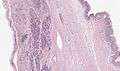

Microscopy

Mucinous cystadenoma of the pancreas